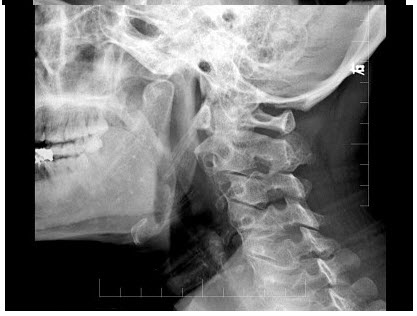

C.门静脉栓塞